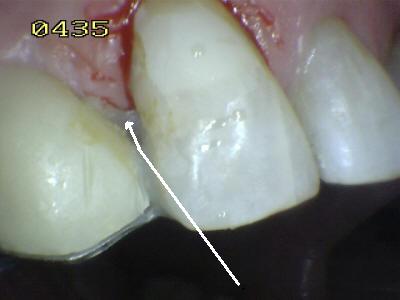

Aspecto vestibular del r3emanente dentario Eliminada la caries, micro-arenado con óxido de aluminio y grabado total con acido ortofosforico (Flechas blancas)

Procedimiento de cementado, se debe tener cuidado de eliminar los excesos de cemento (flechas blancas) antes de su endurecimiento; dado que el espesor de cemento puede ser importante por la desadaptación por caries.